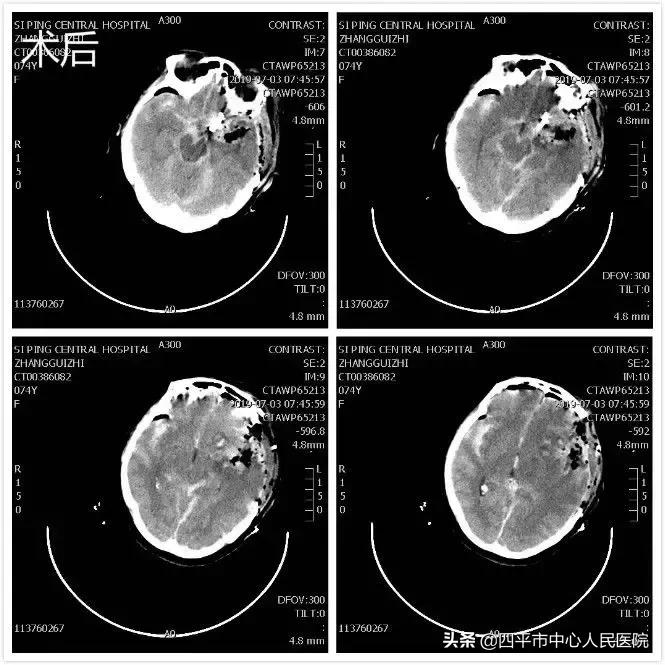

患者张XX,于入院前2小时突发神志不清,伴恶心呕吐,呕吐物为胃内容物,四肢不动,伴尿*禁失**,无抽搐。由家属送至梨树县医院,行头CT检查提示脑出血,为求进一步治疗转送至我院,我院神经内科给予复查头CT提示大量蛛网膜下腔出血,首先颅内动脉瘤破裂所致,由于患者到我院时深度昏迷状态,呼吸微弱,HUNT-HESS分级5级,不适合行头部CTA检查及介入栓塞治疗,家属强烈要求手术治疗,请麻醉科行气管插管后入手术室,李晓东主任带领马龙急诊全麻下经左侧扩大翼点入路行右侧脑室外引流术及颅内动脉瘤探查术,术中探查患者左侧后交通动脉巨大瘤,临时阻断颈内动脉后给予确切夹闭,术中动脉瘤没再次有破裂出血。术后第1天,患者呈浅昏迷状态,刺痛可定位,四肢可自主活动。复查头部CT满意,查头部CTA见左侧后交通动脉瘤夹闭确切。但患者于术后第3天,出现迟发性脑内血肿,考虑到预后不好,家属放弃治疗出院,临出院时对我科李晓东主任及马龙医生的积极救治表示感谢。